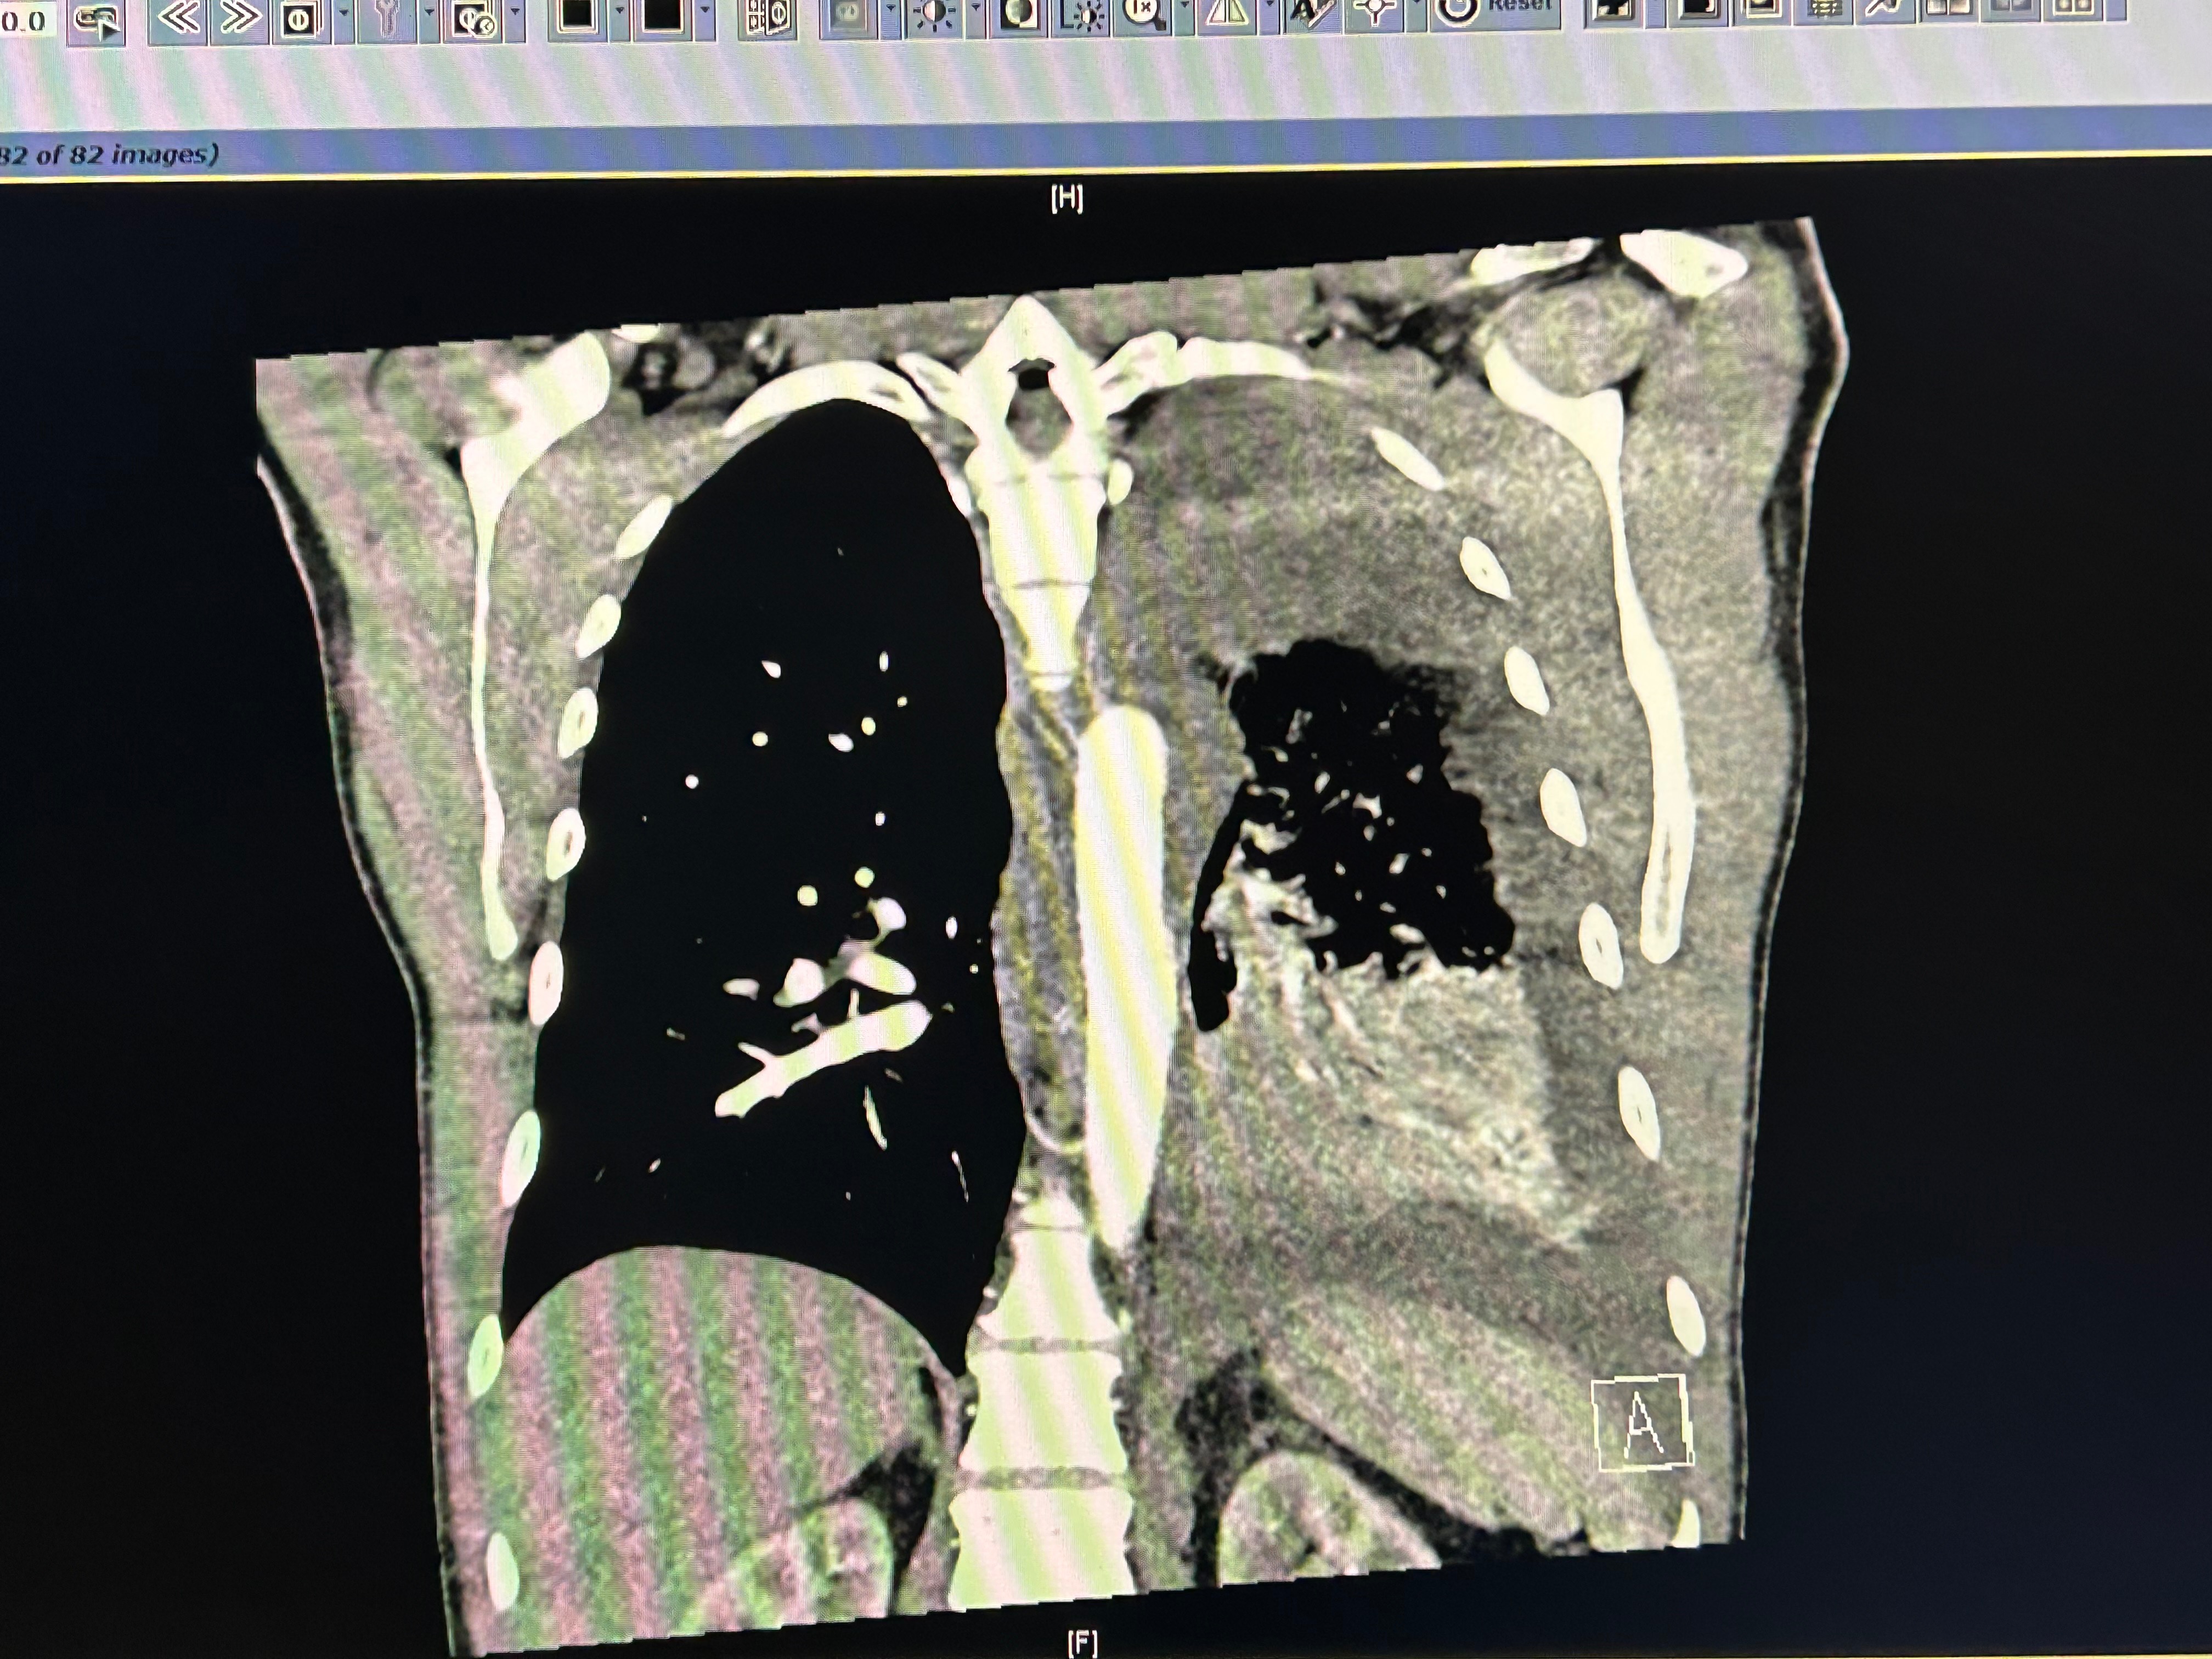

Kevin is the absolute best person in the entire world, and it feels so unfair that was recently diagnosed with stage 4 adenocarcinoma, a form of lung cancer. Our family has been navigating a whirlwind of emotions and challenges since his diagnosis, and we are doing everything we can to support him through this fight. The reality is that cancer treatment comes with overwhelming costs, and we are facing high deductibles, copays, weekly medication expenses, travel for appointments, and out-of-pocket drugs and treatments that aren’t covered by insurance. Every week brings new bills and decisions, and it’s been difficult to keep up with the financial strain while focusing on Kevin’s health and well-being.